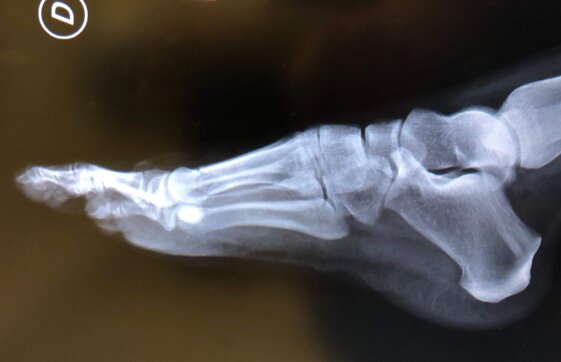

Radiografie post-operatorie in AP e LL di intervento di correzione di Alluce Valgo con tecnica mini-invasiva senza utilizzo di mezzi di sintesi metallici. Per l’osteotomia di correzione del I MT ho utilizzato un pin riassorbibile che quindi non è visulizzabile alle radiografie, mentre per l’osteotomia della prima falange del primo dito non ho utilizzato alcun mezzo di sintesi